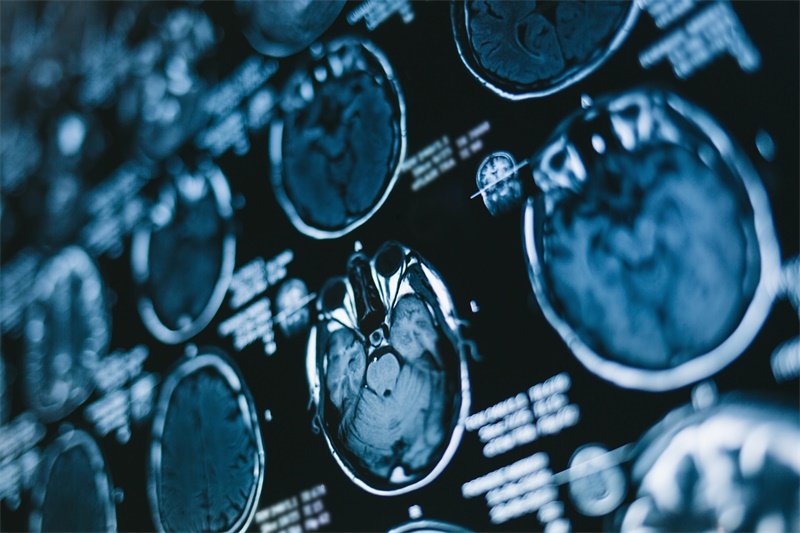

现代医学中,影像学检查是大脑镰旁占位病变诊断的主要手段。最常用的检查方法有:

磁共振成像(MRI)

MRI是最常用的影像学检查之一,可以清晰地显示大脑的结构变化。通过对比不同扫描序列,医生能够获得病变的详细信息,包括大小、形态和与周围组织的关系。

计算机断层扫描(CT)

CT扫描对于急性脑出血等疾病的诊断非常有效,它能够快速提供脑部的三维影像。不过,在某些情况下,CT可能无法提供足够的病变细节,因此往往需要与MRI结合使用。